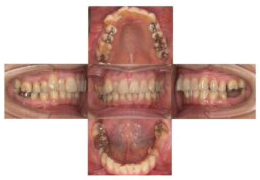

治療前-治療後

(治療前:写真左)

53歳8か月 叢生が気になり笑顔がぎこちない感じです

(治療後:写真右)

矯正治療後は大きなスマイルができるようになりました。

下顎左側の第一大臼歯が欠損しています。ブリッジが外れています。

顎関節にアプローチし、抜歯した歯を欠損部に移植し、下顎位も安定しています。